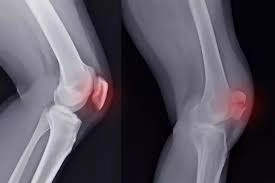

Diz kapağı, yürüme ve hareket kabiliyetinde kritik rol oynayan eklemlerden biri. Bu bölgede hissedilen ağrı ise her yaş grubunda farklı sağlık sorunlarının belirtisi olabiliyor. Günlük yaşam kalitesini düşüren diz kapağı ağrılarıyla ilgili Medikaya Hastanesi Ortopedi ve Travmatoloji Uzmanı Op. Dr. Gökhan Temelli önemli açıklamalarda bulundu.

Vücut ağırlığını taşıyan ve hareket sırasında yoğun şekilde çalışan Diz kapağı, yürüme ve hareket kabiliyetinde kritik rol oynayan eklemlerin başında geliyor. Bu bölgede hissedilen ağrı ise basit zorlanmalardan, ciddi ortopedik rahatsızlıklara kadar farklı nedenlerle ortaya çıkabiliyor.